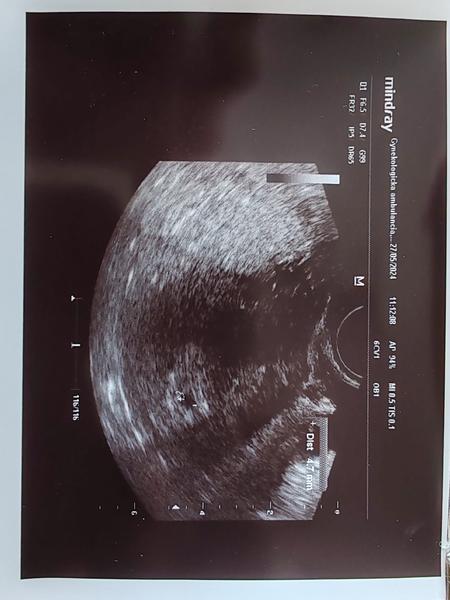

@mirka17 Tu je lepšia fotka ta prvá bola taka na rýchlo no je to jedna a tá istá.

Dobrý deň tak dneska som bola povedala mi že je to strašne maličké že ak príde menštruácia tak to môže zobrať 😔 ja na tom ultrazvuku skoro nič nevidím. Povedala mi že ona tam vidí len vačok. Dneska podľa menštruácie vychádza že by som mala byť v 6.Týždni. V piatok idem znovu. Vôbec neviem čo si mám o tom myslieť. Je to ťažké pre mňa. Ďakujem Vám všetkým za rady a odpovede.

@vevericaxxl vacok je zaklad, uvidi sa v piatok ci bude aj nieco viac. Datum poslednej menstruacie je len orientacny, ovulacia mohla nastat neskor. To cakanie je mucive ale je to dan za to ze to chceme vediet tak skoro. Pokracujem v silnom drzani palcov ❤️

@vevericaxxl myslim,ze by uz vidno malo byt.ja som bola na prvom usg v treťom tyzdni a plod bolo vidieť